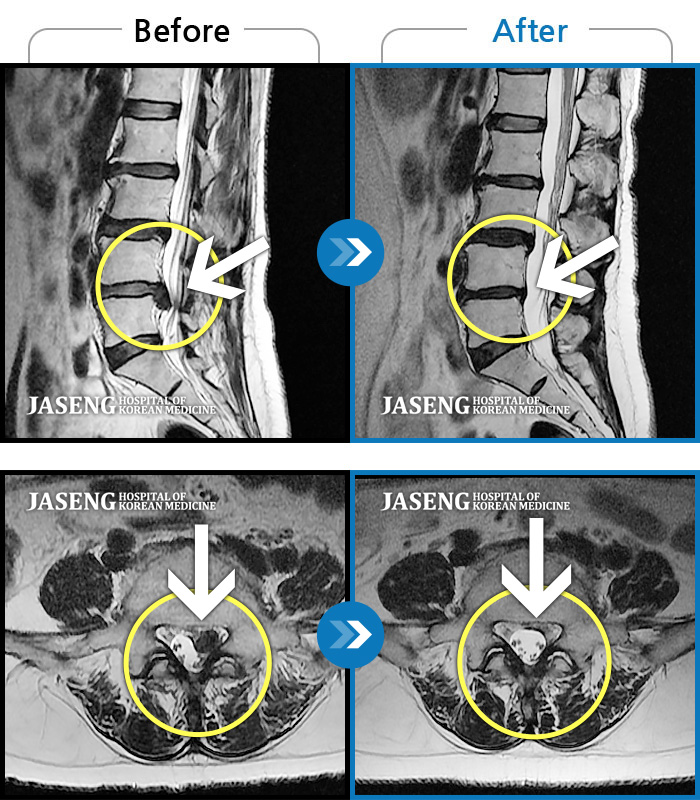

MRI 치료사례

허리 통증, 야간통으로 내원